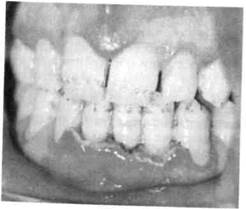

Гипертрофический гингивит представляет собой чаще всего хронический процесс и характеризуется пролиферацией десны на различных участках. Часто отмечается гипертрофия передних отделов верхней и нижней челюстей (рис. 8.5).

Существенную роль в развитии такого гингивита играют гормональные сдвиги (пре- и пубертатный периоды развития ребенка, во время беременности), дефицит витамина С. Кроме того, гипертрофический гингивит нередко развивается при лечении детей с эпилепсией некоторыми препаратами (ди-фенин, гидантоин), реже при болезнях крови (лейкемические рети-кулезы). Наиболее частой местной причиной развития такой патологии является скученное положение зубов в переднем отделе верхней и/или нижней челюсти. Очаговый гипертрофический гингивит развивается под действием механической травмы (кламмер ортодонтического аппарата, нависающие края пломб, кариозный процесс придесневой локализации).

Течение гингивита хроническое, сопровождается деформацией рельефа десны, увеличением межзубных сосочков и десневого края. Различают 3 формы заболевания: фиброзную, гранулирующую (отечную) и смешанную.

В большинстве случаев преобладает продуктивный фиброзный процесс, при котором десневой край слабо кровоточит или не кровоточит, больных беспокоит лишь необычный вид десны. При гранулирующей (отечной) форме десна темно-красного цвета, отличается значи-

Рис. 8.6. Гипертрофический гингивит после приема дифенина.